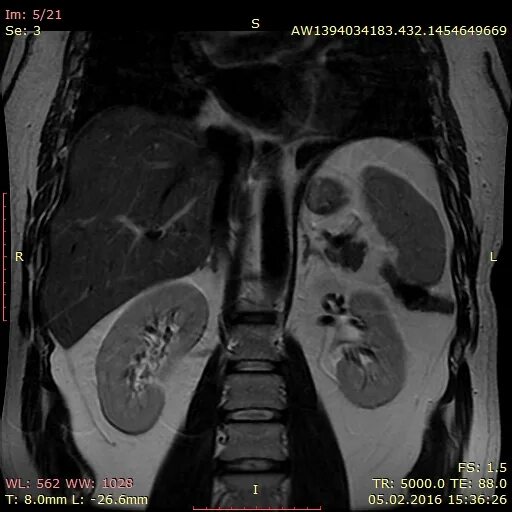

Что входит в мрт забрюшинного пространства